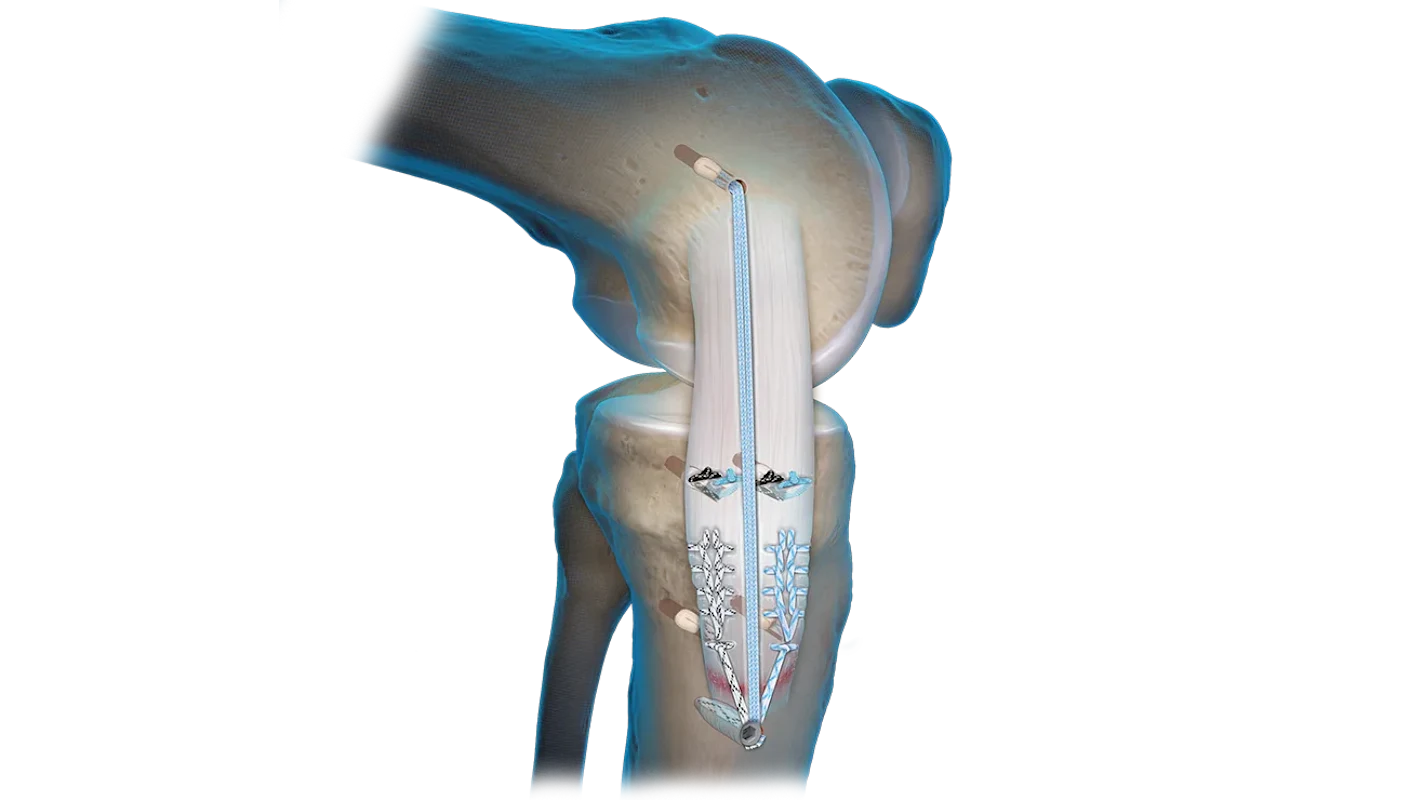

- Implantes para reconstrucción de LCA/LCP

- Suturas meniscales